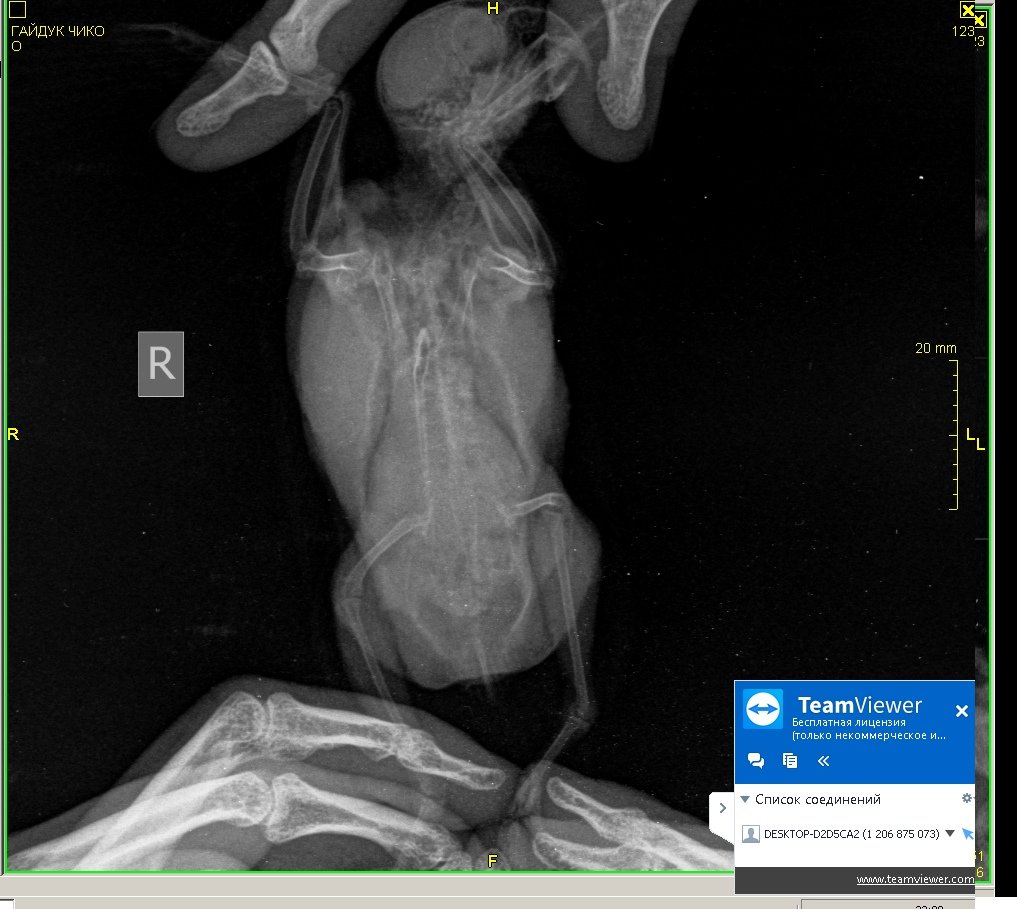

Здравствуйте, нужна помощь! Попугай волнистый, Чико. Возраст - 1,9 3 июня начал без остановки чесать попу, выдергивать перья сзади, вести себя беспокойно. 4 июня отвезла к врачу-орнитологу Полозу, взял мазок из зоба и посмотрел кал под микроскопом - определил Гельминтоз, выписал метронидазол 10 дн, решила показать др врачу - Грязнову. 5 июня - отвезла, глянул в микроскоп калл - сказал, что "единичные случаи паразитов", добавил к лечению Нистатин, посоветовал рентген, сделала рентген, но врачам из Минска не показывала , тем,у которых была на приеме, показала знакомому ветеринару -Валерии Сороке, на ее взгляд возможны проблемы с легкими, вчера заметила, что Чико чихнул мокрым! Также сейчас у него зеленый помет, возможно от метронидазола. Совсем я в рестерянности, продолжать лечить глистов? или лечить легкие? Валерия прописала следующие препараты:1. амоксиклав 125 мг 0.2 мл 2 раза в день 14 дней ( 1/2 табл растворить в 2 мл воды) 2. флуканазол 50 мг внутрь 1/10 капс 1 раз в день 14 дней 3. метронидазол 4. иммунофан Помогите поставить точный диагноз по снимку, у нас как таковых орнитологов нет... Сейчас поведение птицы: веселый, активный, кушает хорошо, чешется, чешет попу, чихи мокрые редко.